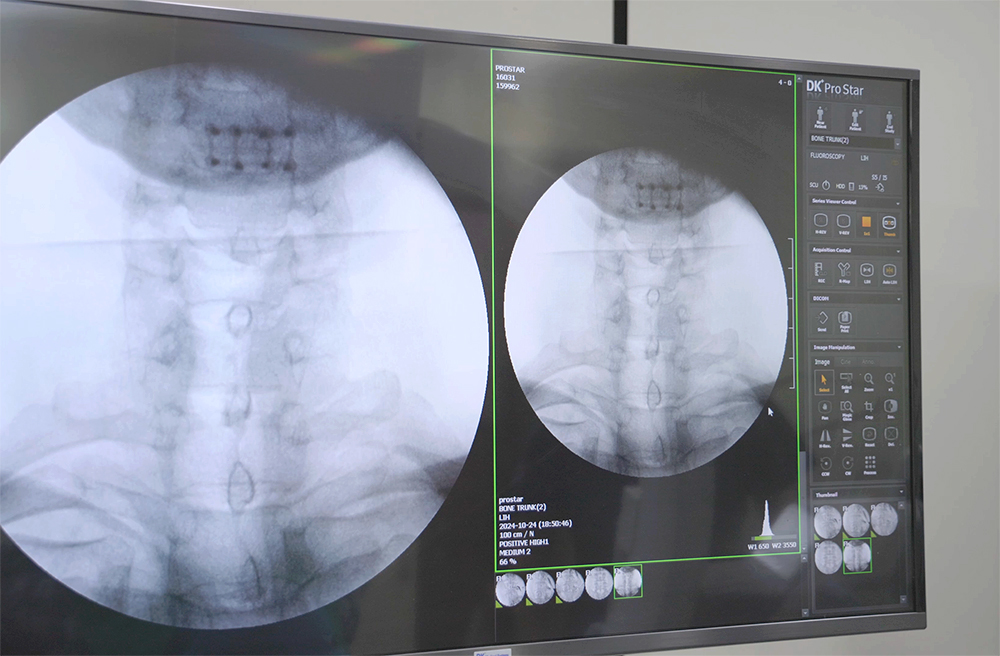

추간판조영술 사진 1

추간판조영술 사진 2

추간판조영술

디스크탈출증은 MRI로 진단이 가능하지만, 디스크내장증은 디스크 속에서 통증이 발생하는 질병이기 때문에 MRI를 찍어도 진단이 불가능합니다. 추간판조영술이라는 검사를 통해 디스크내부에서 통증이 생기는지 직접 확인을 해야만 진단이 가능합니다.